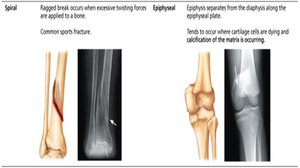

Spiral | Ragged break from excessive twisting forces. Common sports fracture. |

Epiphyseal | Epiphysis separates from diaphysis along epiphyseal plate. Occurs where cartilage cells are dying. |